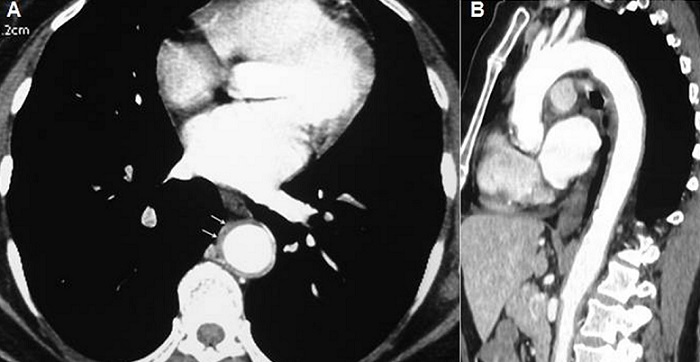

La maladie de Horton est une vascularite segmentaire et focale qui touche les artères de gros et moyen calibre, intéressant préférentiellement les branches de l'artère carotide externe. L'atteinte aortique est observée dans 5 à 15 % des cas, mais elle est probablement sous-estimée en raison d'une symptomatologie souvent pauvre ou peu spécifique. Elle est rarement inaugurale et survient le plus souvent lors de la décroissance de la corticothérapie. Nous rapportons l'observation d'une patiente âgée de 75 ans, hospitalisée pour exploration d'une fièvre prolongée associée à un syndrome inflammatoire biologique. A l'anamnèse, la patiente rapportait des céphalées fronto-pariétales depuis un mois. Il n'y avait pas de notion d'altération de l'état général, ni de sueurs nocturnes, ni de signe de pseudo polyarthrite rhizomélique. L'examen clinique était normal. Les pouls temporaux étaient pulsatiles. Le bilan biologique montrait une anémie à 8,6 g/l, une vitesse de sédimentation à 132 mm à la première heure, une protéine C réactive à 68 mg/l, une fibrinémie à 8,8 g/l et une hyper-alpha2-globulinémie. Les anticorps antinucléaires et les ANCA étaient négatifs. La recherche d'un foyer infectieux pulmonaire, ORL, stomatologique et urinaire était négative. L'échographie transœsophagienne ne montrait pas des signes en faveur d'une dissection aortique ou d'une endocardite. En l'absence de point d'appel, une tomodensitométrie thoraco-abdominale a été réalisée, mettant en évidence un épaississement pariétal régulier et circonférentiel intéressant l'aorte thoracique, les troncs supra-aortiques, l'aorte abdominale et les artères iliaques primitives à leur origine. La biopsie d'artère temporale montrait un aspect d'artérite temporale à cellules géantes. Un traitement par corticoïdes à raison de 1 mg/kg/j était instauré, entrainant une disparition rapide de la fièvre et des céphalées et une régression du syndrome inflammatoire.